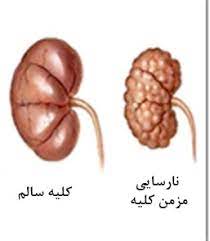

قیمت: 32٬000 تومان - دسته بندی فایل: علوم پزشکیپاورپوینت نارسایی مزمن کلیه

فروش ویژه پاورپوینت حرفه ای نارسایی مزمن کلیه با تخفیف استثنایی فقط 62453 هزار تومان تعداد اسلاید : 27 اسلاید